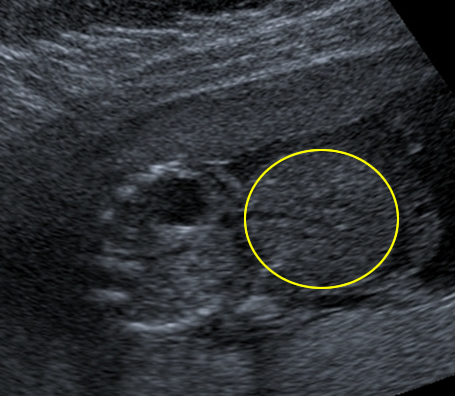

This axial scan through the fetal abdomen might lead you to believe that there are two babies lying side by side.